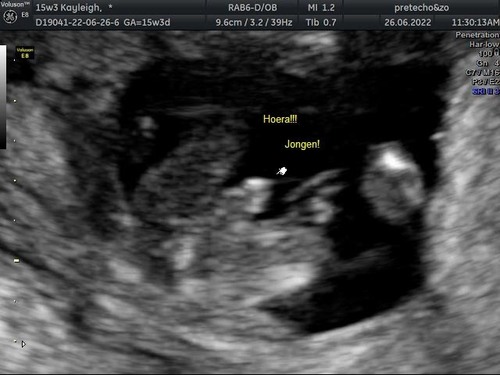

Ik vind het heel erg op mijn echo foto lijken en daar zeiden ze overduidelijk een jongetje. Maar ik ben echt slecht met echo foto鈥檚 dus zou het niet durven zeggen

Reactie op Lelie99

Ik vind het heel erg op mijn echo foto lijken en daar zeiden ze overduideli ...

Dit is wel echt een jongen, die van TS een meisje :)

3 jaar geleden

Reactie op xxTessa